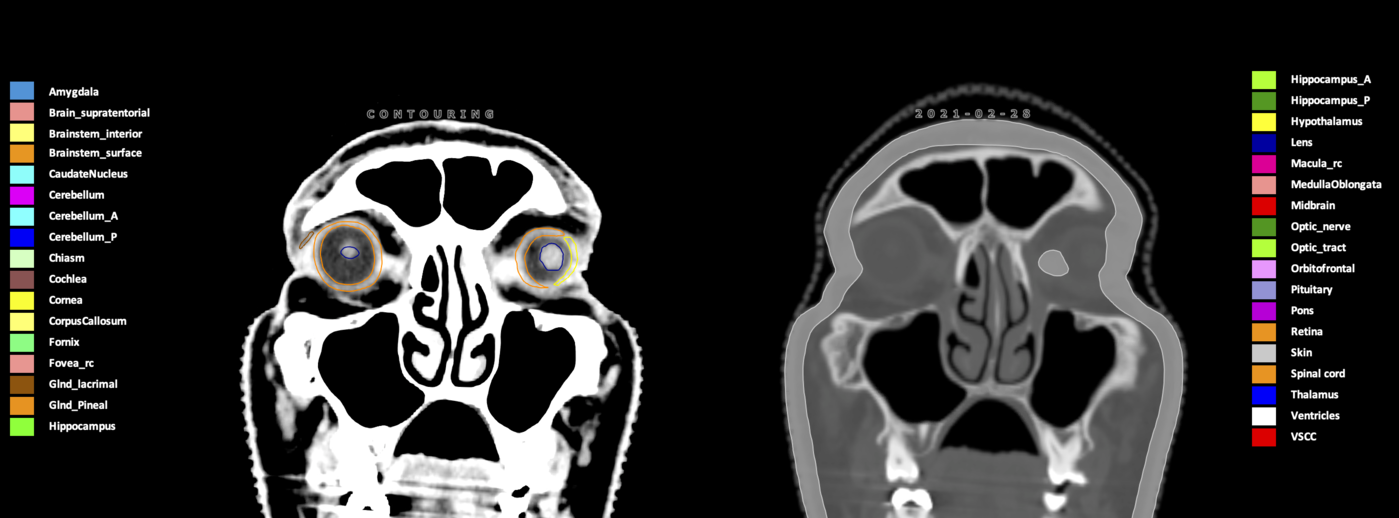

Eekers et al. have published an international neurological atlas for contouring of organs at risk in consensus with the European Particle Therapy Network (EPTN) in 2018 and an update in 2021. The purpose of this consensus atlas is to decrease inter- and intra-observer variability in delineating OARs relevant for neuro-oncology.

Included are all OARs known to be relevant for radiation-induced toxicity in neuro-oncology: brain, brainstem (midbrain, pons, medulla oblongata), chiasm, cerebellum (anterior & posterior), cochlea, cornea, hippocampus (anterior & posterior), hypothalamus, lens, lacrimal gland, optic nerve, pituitary, skin, and vestibular & semicircular canals. To further facilitate research on cognition, vision and radiological changes after irradiation of the brain, potential clinically-relevant OARs are included: amygdala, caudate nucleus, cerebellum (anterior & posterior), corpus callosum, fornix, macula, optic tract, orbitofrontal cortex, periventricular space (PVS), pineal gland, and thalamus.

Three-dimensional delineation of the 25 consensus OARs for neuro-oncology are shown on CT (WW/WL 120/40, 3000/600), 3T MR images, (T1Gd, T2FLAIR 1mm) and 7T MR (MP2RAGE 0.7 mm). All are presented in transversal, sagittal and coronal view.